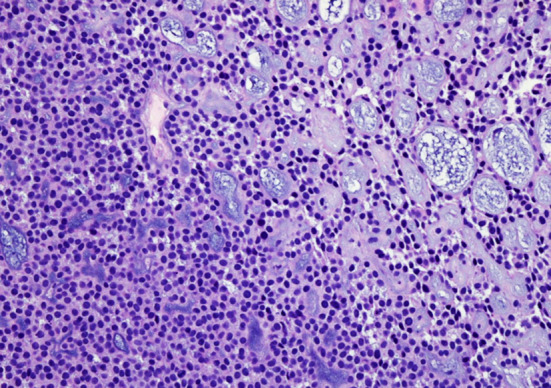

Fig. 4.

Histological features of esophageal AcCC. a The tumor is underneath the squamous epithelium and invade to focal submucosa (25 ×). The original extralobular ducts are destroyed by the tumor, but the ostia of these ducts are marked (arrows). b The tumor is covered by surface squamous epithelium without intraepithelial neoplasia (100 ×). Please note the ostium of SMG duct (arrows). c The minor ductal component of the tumor is adjacent to one SMG (100 ×). d Most area of the tumor shows the acinar differentiation (200 ×). e The tumors cells have a uniform round or oval nucleus and eosinophilic or vacuolated cytoplasm (400 ×). f Mucous cell is rare but detectable (arrow) (400 ×)